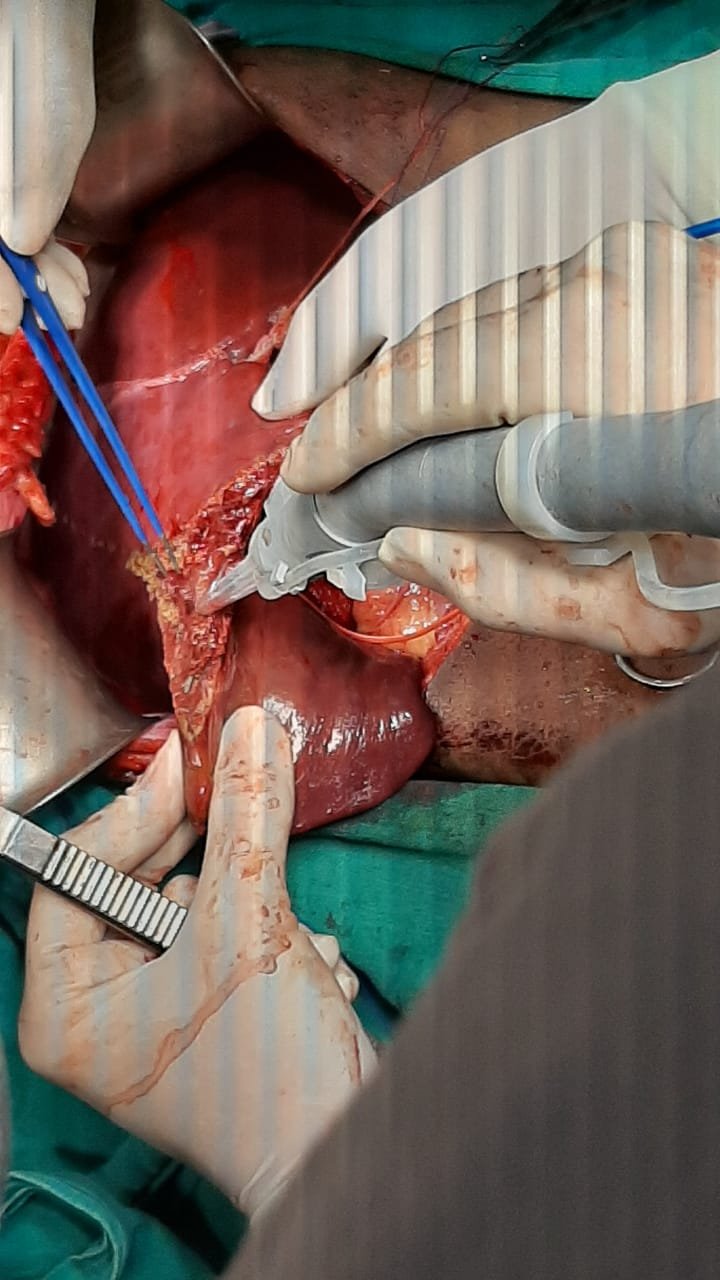

Liver Trauma

A liver injury is some form of trauma sustained to the liver. This can occur through either a blunt force such as a car accident, or a penetrating foreign object such as a knife. Liver injuries constitute 5% of all traumas, making it the most common abdominal injury.

Internal bleeding is one of the most serious consequences of trauma. Usually, the bleeding results from obvious injuries that require rapid medical attention. Internal bleeding may also occur after a less severe trauma or be delayed by hours or days. Some internal bleeding due to trauma stops on its own. If the bleeding continues or is severe, surgery is required to correct it.